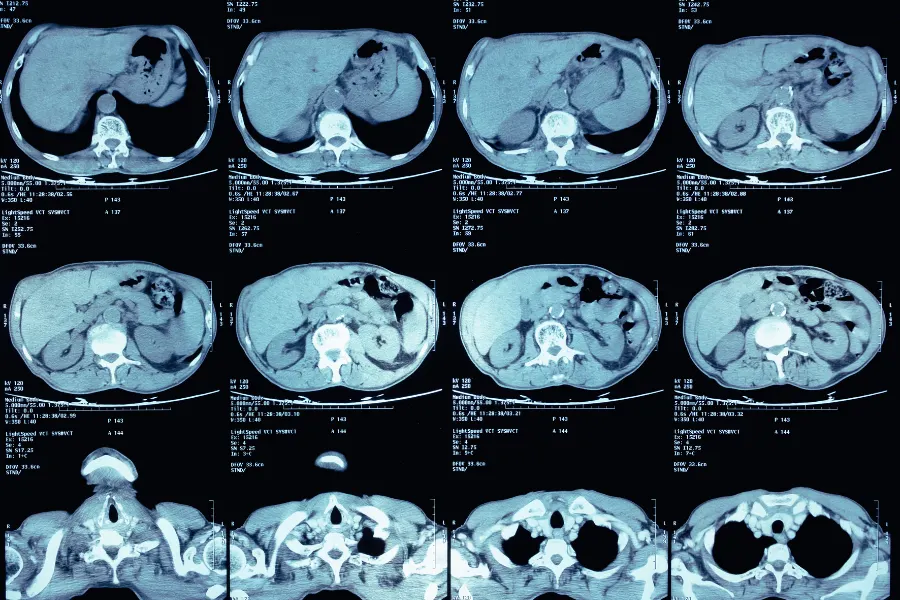

Контрастное КТ позволяет рассмотреть внутренние органы с высокой детализацией и выявить широкий спектр заболеваний — от острых воспалений до онкологических процессов.

Патология печени.

Контрастное исследование выявляет жировую дистрофию, гепатит, цирроз, кисты, сосудистые мальформации и опухоли. Оно помогает отличить доброкачественные образования от метастатических очагов.

Поджелудочная железа.

Обнаруживает острый и хронический панкреатит, кисты, опухоли, нарушения проходимости протоков, оценивает кровоснабжение и возможные осложнения.

Почки и мочевыделительная система.

Диагностирует камни, пиелонефрит, опухоли, гидронефроз, а также тромбозы и аневризмы сосудов.

Сосудистые заболевания.

Помогает диагностировать аневризмы, тромбозы, стенозы, ишемию кишечника, внутренние кровоизлияния.

Онкология.

КТ с контрастом — ключевой метод при диагностике и стадировании рака, определении метастазов и контроле эффективности лечения.